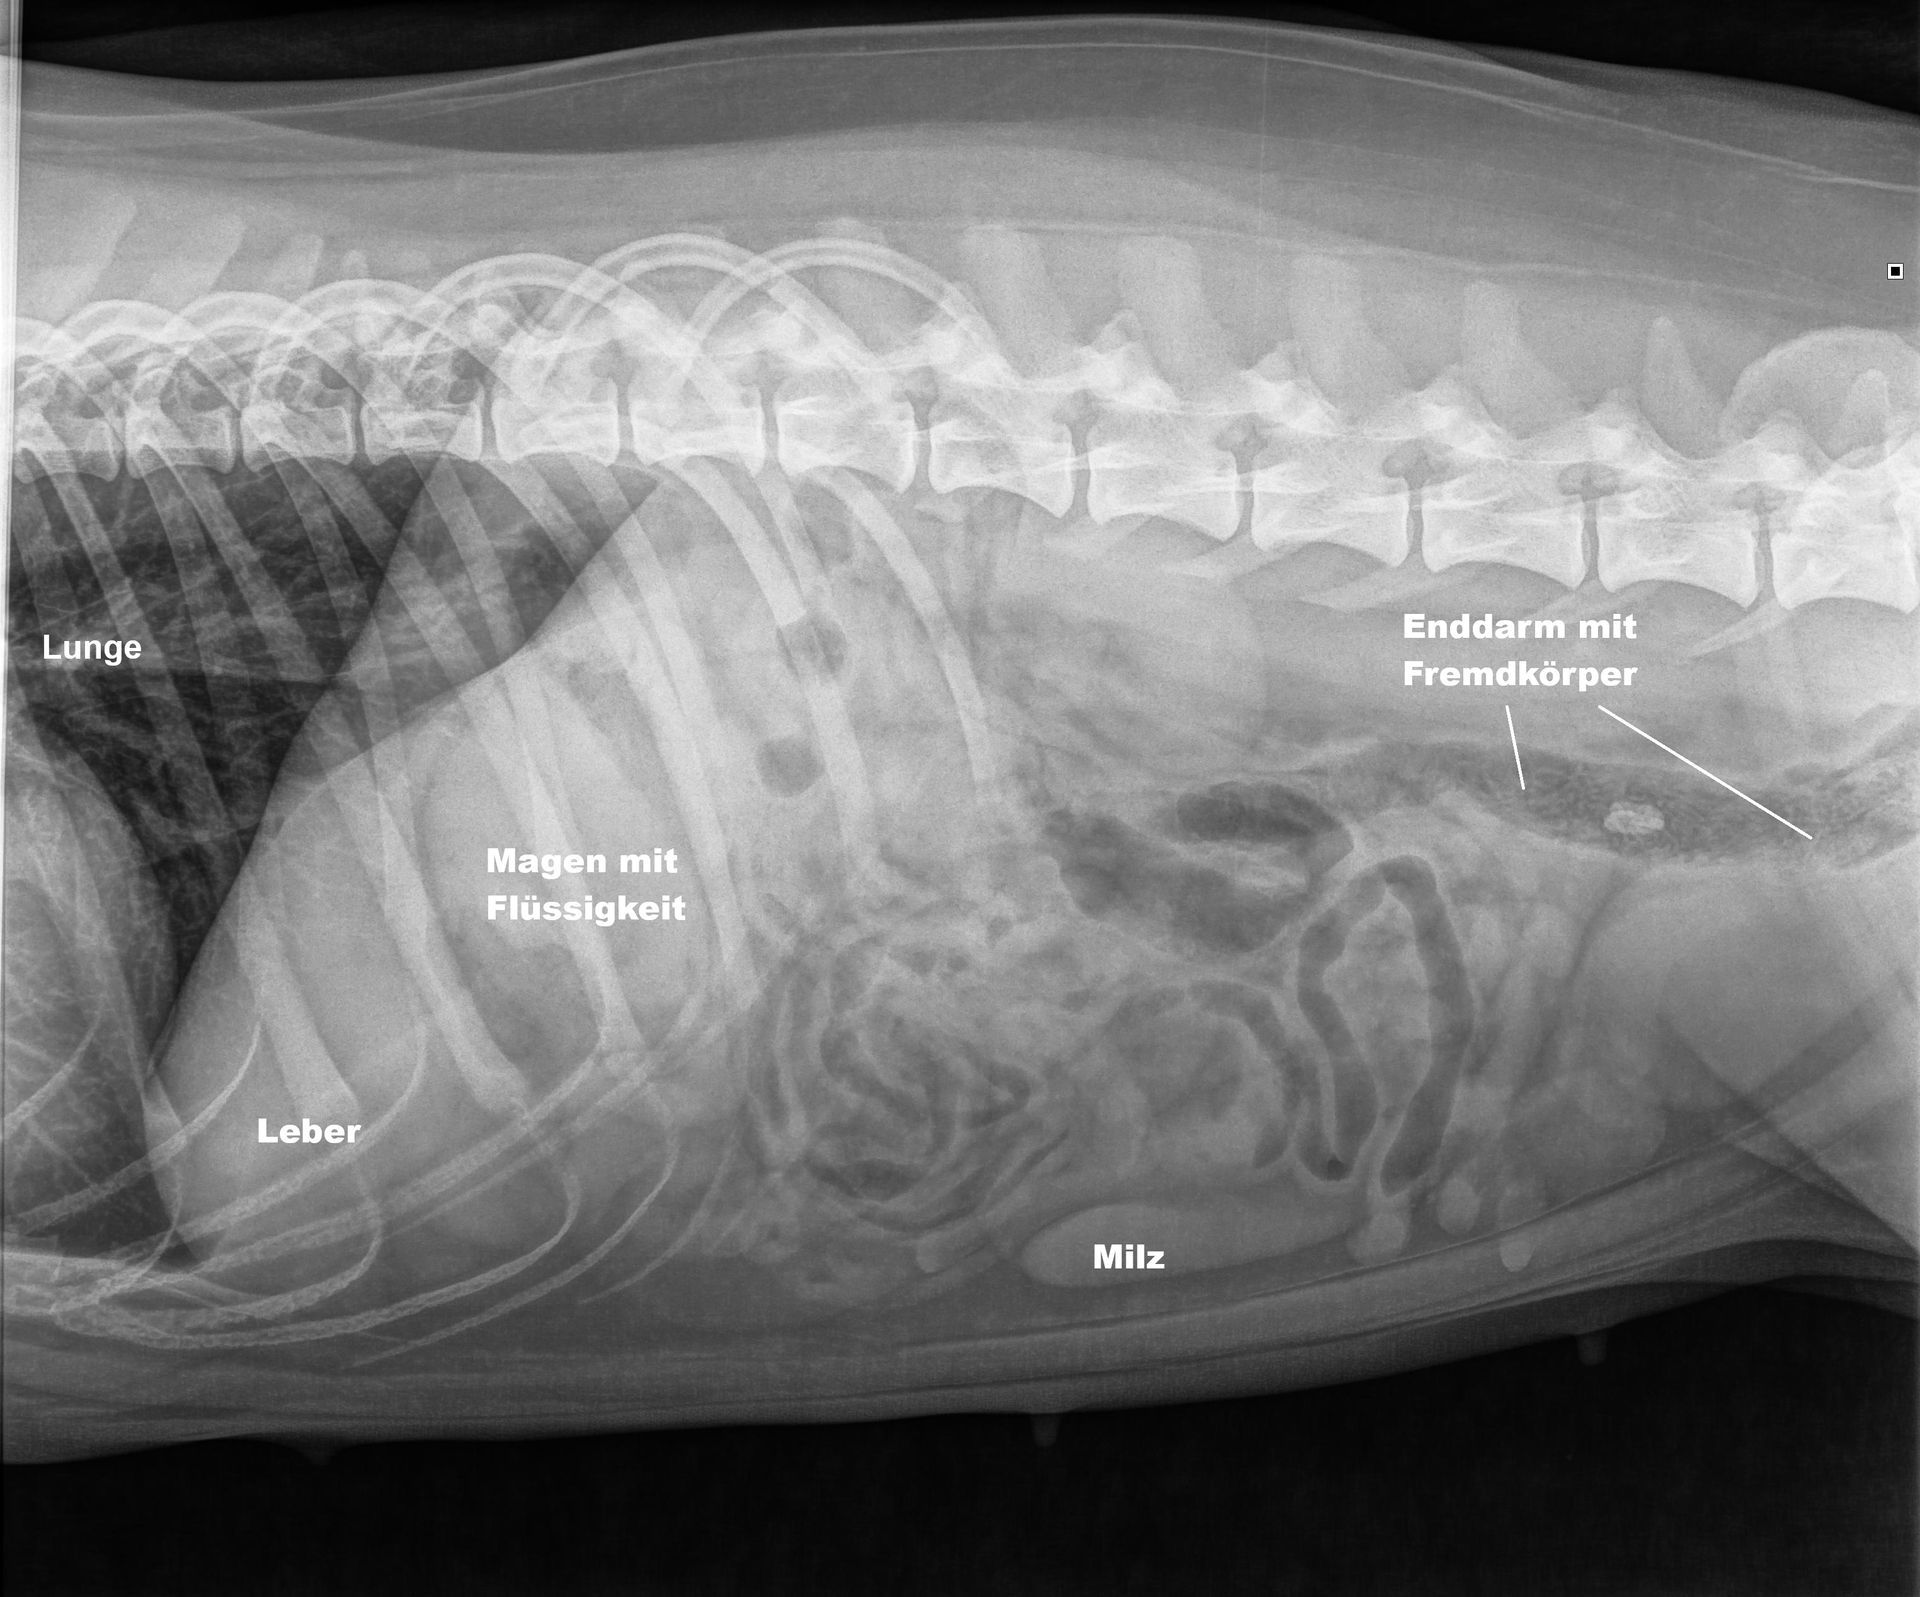

Im Röntgen ist erkennbar, dass der Fremdkörper mit grösster Wahrscheinlichkeit schon den ganzen Dünndarm passiert hat und sich im Dickdarm befindet. Der Magen enthält etwas Flüssigkeit, weshalb radiologisch nicht ausgeschlossen ist, dass sich auch hier noch Teile des Fremdkörpers befinden könnten. Der Dünndarm zeigt zum Glück keine Anzeichen eines Darmverschlusses.